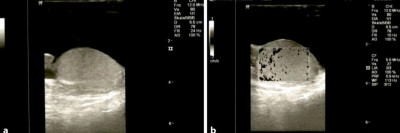

Relikt aus der Kindheit verursacht Leistenschmerz bei Frau

Eine Schwellung bis unter das linke Leistenband nimmt bei einer 64-jährigen Patientin seit einigen Monaten immer mehr zu, so wie ihre Schmerzen in den letzten Wochen. Eine sichtbare Rötung oder Überwärmung ist nicht vorhanden, aber eine kleine Bruchlücke tastbar. Ursache war etwas, was eigentlich im ersten Lebensjahr verschwunden sein sollte.